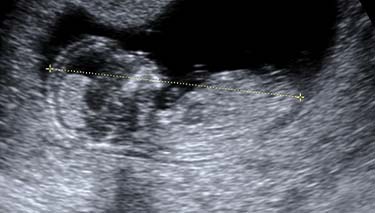

A 2D ultrasound is the standard procedure used during obstetric ultrasound. It is the one used to produce 2 dimensional images of what is happening inside the mothers and baby's body. Generally, all pregnancy ultrasounds are still done using 2D technology. A baby's gestation, growth, heartbeat, development and size can all be seen clearly using 2D ultrasound. The position of the placenta, cord and lie/position of the baby can also be clearly seen.

The images from a 2d ultrasound tend to be in black and white and have the same level of detail as a photographic negative. Depending on how the baby is lying and their position in the uterus, different images will be seen.